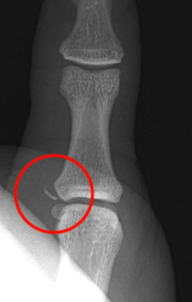

X-ray

Bony avulsion

1. Small fragment pulled away from proximal phalanx